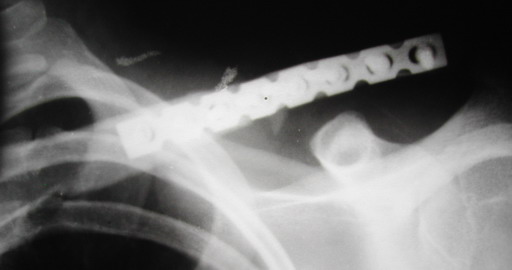

Один из вариантов, что удалось быстро найти, позже еще найду, но схема примерно такая (первое

вложение).

Мужик кочегар, срок нетрудоспособности 7 недель. Наружную конструкцию сняли через 3 недели. Далее без иммобилизации. Погруженную спицу можно убрать и через несколько месяцев, если жить не мешает.

Раньше не погружали, на рентгенограммах и натуре видно (последние 2 вложения). Как вариант спицы в периферическом отломке могут крепится на трехдырочную приставку, что дает возможность компрессии.